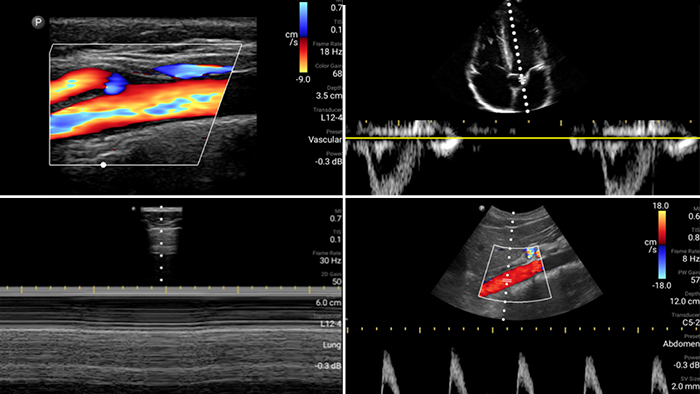

Lumify is with you every step of the way

Evaluate, diagnose and treat your patients in minutes with a multi-point POCUS exam.